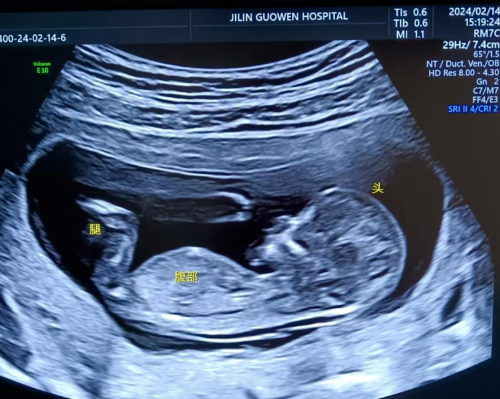

產(chǎn)科 Obstetrics Department